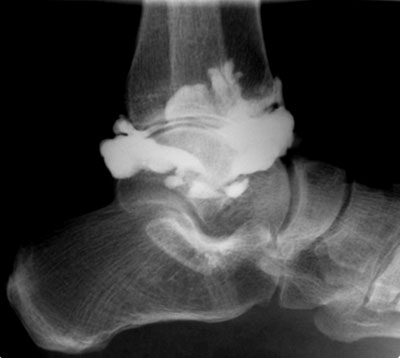

L'arthrographie est un examen radiologique consistant à introduire un produit de contraste en intra-articulaire (apparaissant en blanc sur les clichés) afin de démontrer l'intégrité ou la présence de lésions de structures intra-articulaires comme les cartilages, les ligaments, etc.

L'arthrographie est donc une technique qui utilise les rayons X et des agents de contraste qui sont en principe à base d'iode. Les articulations les plus fréquemment examinés sont l'épaule,le genou, le poignet, la hanche et la cheville.